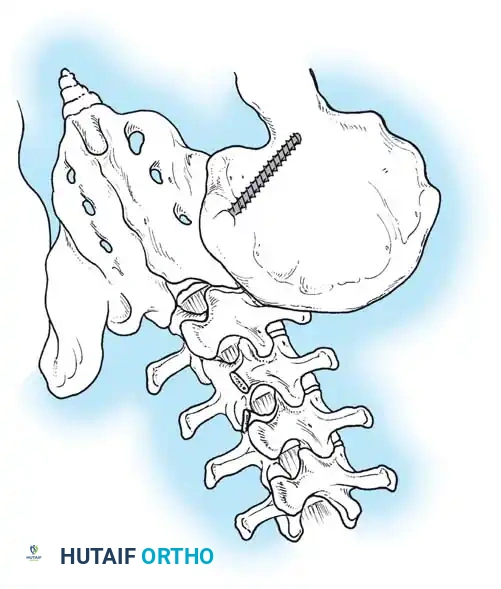

Evaluating Pelvic Obliquity

Pelvic obliquity is a primary driver of seating imbalance and decubitus ulcer formation over the ischial tuberosities. The surgeon must differentiate between a fixed spinopelvic deformity and obliquity caused by infra-pelvic contractures.

NEUROMUSCULAR SCOLIOSIS Surgical Diagram

• A: Clinical presentation of pelvic obliquity.

• B: If the pelvic obliquity resolves with abduction or adduction of the hips, the primary cause is a pelvic-femoral muscle contracture (infra-pelvic).

• C: If the obliquity persists despite hip positioning, a fixed spinopelvic deformity exists, necessitating fusion to the pelvis.

Image

Surgical Warning: Failure to recognize and release severe hip contractures prior to or concurrent with spinal fusion will result in persistent seating imbalance and immense stress on the distal spinopelvic instrumentation, leading to catastrophic hardware failure.